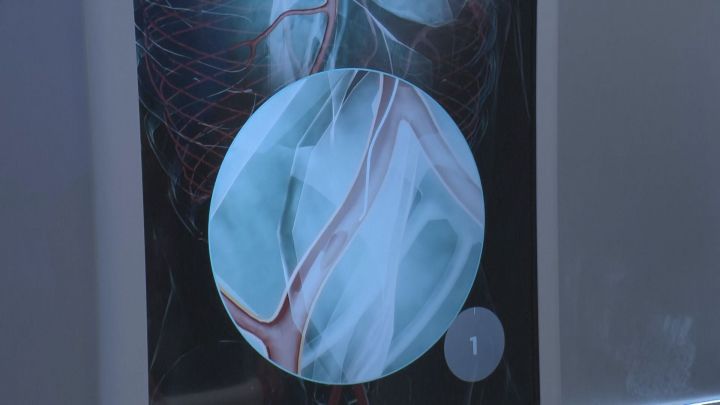

■脈打つ約3.5cmの心臓が…朝日インテックらが「未来の医療」の体感

愛知県瀬戸市の医療機器メーカー「朝日インテック」がパソナグループと共同で出展しているパビリオン『PASONA NATUREVERSE』では、未来の医療を体感できます。 将来実現を目指している3Dの技術が活用されたカテーテル治療のコーナーがあり、手元のコントローラーを操作することで、モニターに映った血管にワイヤーを通していく治療が体験できます。

他にも、特殊なアームとゴーグルを装着した人間と、離れた場所にいても同じ動きをするロボットや…。

iPS細胞から生まれた3.5センチほどの心臓も展示されています。

実際の心臓と同じ機能ではないものの、人の体温に近い培養液に浸すことで、ドクドクと脈を打つように動きます。